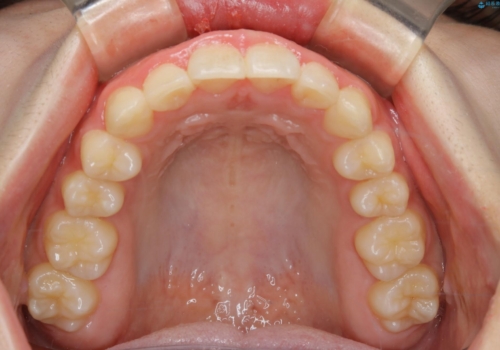

前歯のがたつきとディープバイト:インビザライン治療

- 前歯のがたつきと、噛み合わせが深いことを気にされてご相談にいらした方です。

インビザラインにて治療を行いました。

一般的に、歯冠(歯の長さ)が短い方はインビザライン治療に時間がかかりやすい傾向にあります。

歯の移動量に対して大きなブラックトライアングルもできることなく綺麗に並べることができ、大変喜んでいただけました。